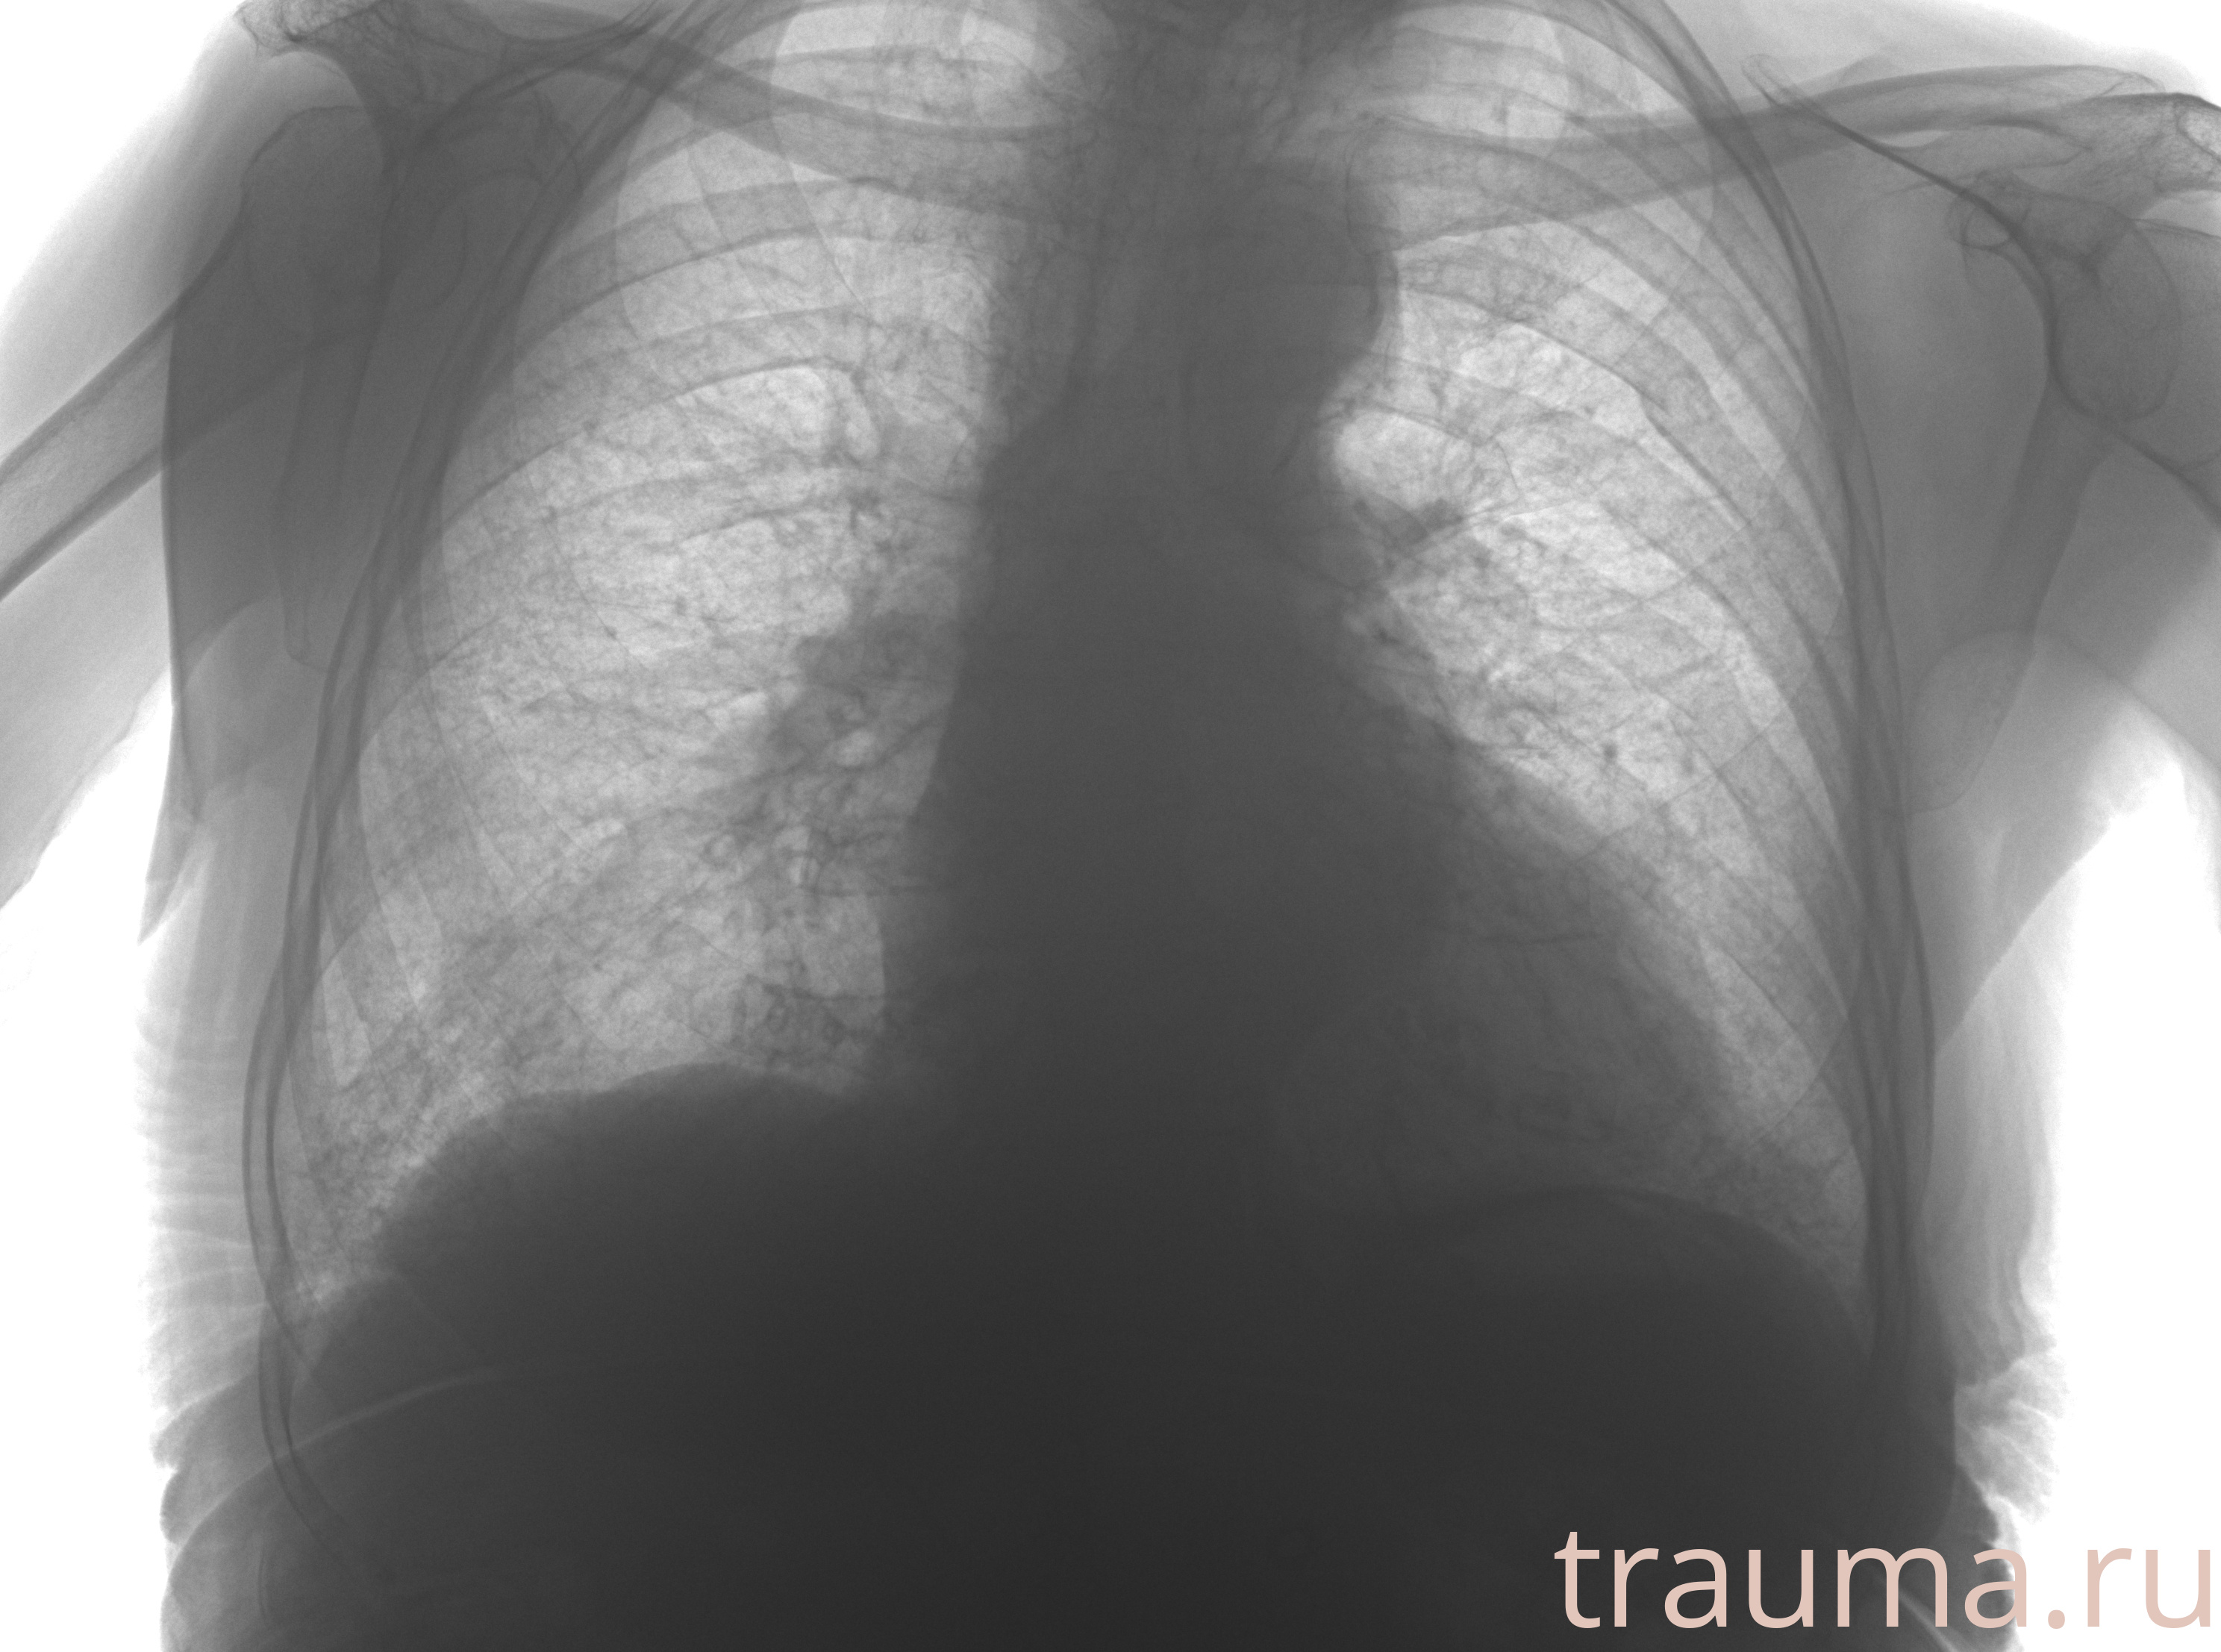

Рентгенограммы

Рентген на дому: по вашему адресу приезжает врач-рентгенолог, травматолог-ортопед с мобильным рентгеновским аппаратом, проводит диагностику травмы или заболевания, делает необходимые рентгенограммы, дает рекомендации по дальнейшему лечению. Получить качественные снимки в домашних условиях возможно благодаря уникальной методике, разработанной МосРентген Центром для института  Склифосовского